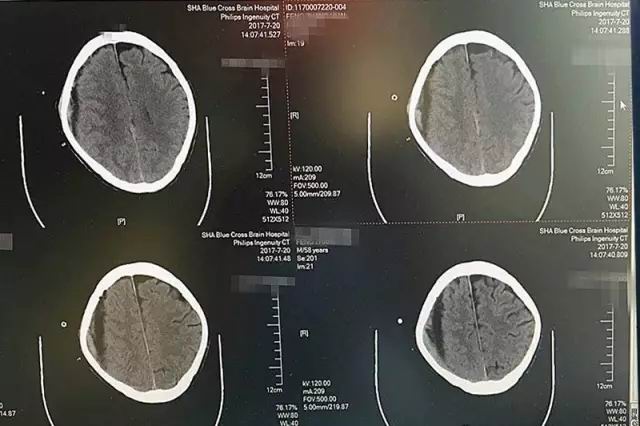

即便如此,时间不等人,等到七月中旬老冯一家辗转打听到上海蓝十字脑科医院,慕名找到神经内科的李振并主任时,老冯的症状已经开始加重了。入院时的脑CT影像检查显示,患者出血量增加,脑中线明显移位变质,左侧肢肌力3级(在和地心引力相反的方向中尚能完成其动作,但不能对抗外加的阻力),而且,他开始出现嗜睡、不思饮食的情况,如果再不及时治疗,患者很可能会陷入昏迷、偏瘫、失语、癫痫,巨大的风险正一步一步靠近。因此,迅速制定合理的治疗方案,才能及时挽救患者。

患者术前CT影像显示:红圈处为脑出血部位,出血量较大,颅内压升高

患者术后CT影像显示:血肿基本被吸收